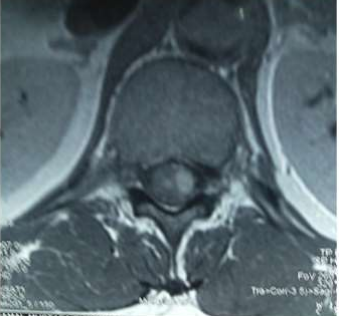

Eight of the ten patients were diagnosed utilizing MRI which showed Dorsal 12 to Lumber 1 or 2 spinal cord swelling with hyper intense patches in T2 images , while the remaining two patient were diagnosed utilizing CT myelogram which showed Dorsal 12 to Lumber 1 or 2 spinal cord swelling.

Image (7) Sagittal MRI of the Case No (5) Showing cord expansion at the level of conus medullaris with absence of subdural space and some hyperintense patches

Image (8) Sagittal MRI of the Case No (7) Showing cord expansion at the level of conus medullaris with absence of subdural space and some hyperintense patches.

Image (9) Axial MRI of the Case No (7) Showing cord expansion with absence of subdural space and some hyperintense patches